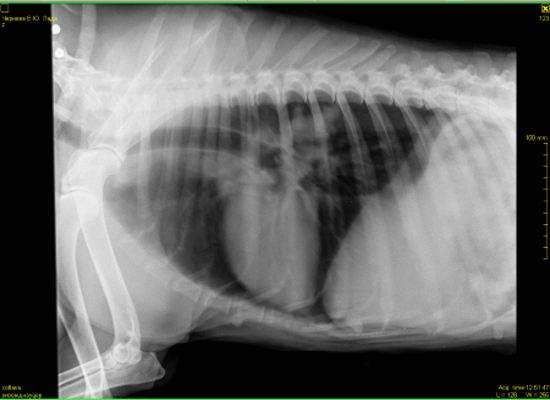

Всем доброго дня.Наши последние сводки с фронтов.В субботу мы сделали рентген.В программе,когда врач нам объяснял ситуацию,конечно было все более наглядно.Сейчас я не совсем понимаю,почему именно эти снимки открыты для доступа и почему именно их он записал.По словам врача у нас есть все ж изменения в области средостения в лимфаузлах. Что-то давит на пищевод.На снимке он должен быть прямой ,а он немного изогнут. Увеличено с одной стороны сердце и есть затемнения в легких справа(врач заметил именно затемнения,а не образования).По мне так совершенно ничего не понятно,а только больше вопросов возникло у меня.Нам назначили УЗИ и посещение кардиолога.Отсюда вопрос.Есть ли у кого ценный врач-кардиолог в районе СВАО? Операция по прежнему под ОЧЕНЬ большим вопросом.Лада пьет лекарства.Немного вялая от них.Гуляет ,кушает,спит и играет в мячик.Кашляет.

Прилагаю нашу добычу.

В легких безусловно что то есть.... вопрос что.

Сердце по рентгену не увеличено, у него " сглажена талия", что может быть при перегрузке правого сердца, которое отвечает за легкие . Повышено внутрилегочное давление из за mts в лимфоузлах скорее всего корня легких. Возможно начинает скапливаться жидкость в перекарде, а может все вместе. Мы никак не сможем на все это повлиять. Для всего, что я описала нужно не просто увидите жидкость в перекарде, а померить давление на лёгочной артерии, доплер на узи аппарате нужен. В принципе, что хотели узнать - есть там что то или артефакт. Есть(((. Грядку оперировать? Считаю, что операция только усугубит страдания. Все таки я за антибиотик и дексаметазон, и посмотреть. Клинически может уменьшиться кашель.